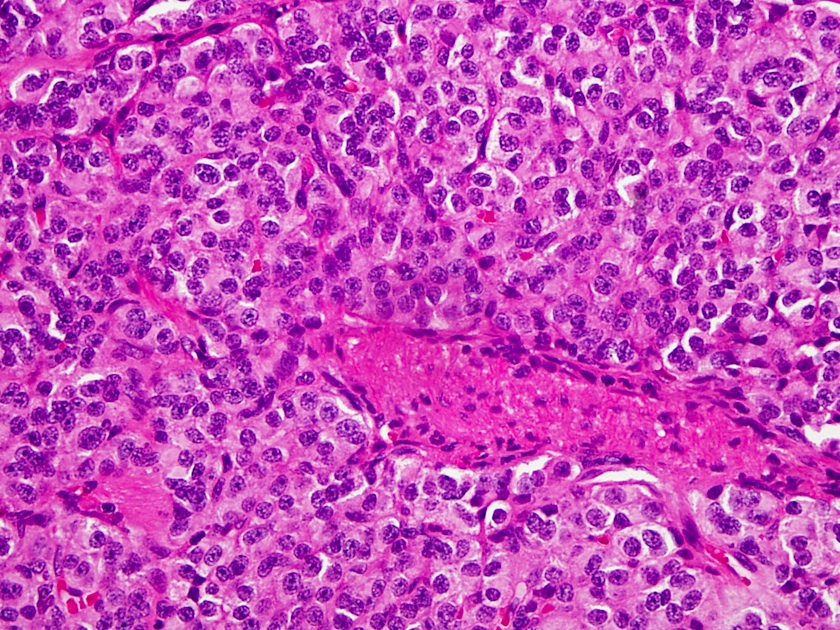

Where do carcinoid tumors come from?

Carcinoid tumors are NETs that primarily arise from enterochromaffin cells located throughout the gastrointestinal (GI) and bronchial tracts . 1,2 These cells are responsible for the production, storage, and secretion of many biologically active substances—including serotonin, norepinephrine, dopamine, histamine, bradykinin, prostaglandins, substance P, and others—that may lead to the development of carcinoid syndrome, a collective term encompassing a variety of symptoms mediated by the hormones secreted by the carcinoid tumor. 1-4

What is neuroendocrine tumor?

Neuroendocrine tumors (NETs) are a heterogeneous group of tumors that arise from enterochromaffin cells with traits of both nervous system and hormone-producing cells. Neuroendocrine tumors are principally characterized by originating site, grade, and stage, as well as functional status. Most (70%) are found in the gastrointestinal (GI) tract, ...